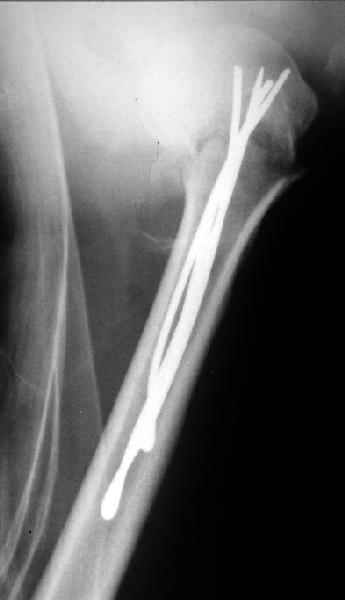

Здесь случай перелома-вывиха плеча, больному 56 лет, после "дважды" закрытой неудачной репозиции, опять же ургентно взяли в операционную, после полного общего обезболивания попытались сделать репозицию, и фиксацию провели спицами.

Больной находился в повязке, примерно напоминяющей косыночную, рекомендованы движения в локтевом суставе и маятниковые движения в плече, спицы удалены в три недели (были случаи миграции)

Больной амбулаторный, предупрежден на случай осложнения АВН головки.